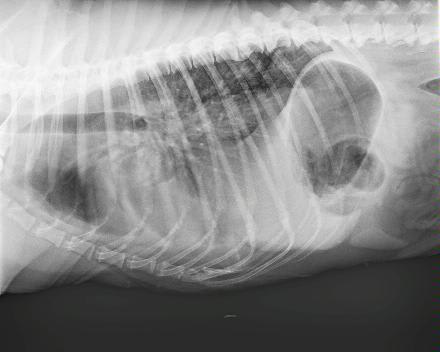

My dog has had a cough for over a month. They said her blood work and xray seem normal. I feel like her breathing is getting a bit worse. Her resting rate is about 35 bpm. She's on doxycioline which doesn't seem to be helping.

You might ask your veterinarian if the X-rays could be reviewed by a radiologist. While the resolution that the forum pictures allow makes them a bit difficult to interpret, I am concerned that the X-rays do not appear normal, and she may have a more serious underlying condition. It may be that she has some underlying heart disease, cancer, or an infection that requires a more broad spectrum of antibiotic. I agree the blood work you've attached is unremarkable. Was a CBC performed as well? Check back with your vet about a radiology review, and a recheck exam as well. A consult with a cardiologist may be recommended, depending on the radiologist's opinion. I'm sorry I don't have better news, or a solution to offer you to try at home, but I think you need to circle back and followup with your vet on this. Thank you for asking Petco Pet Education Center, formerly Petcoach.